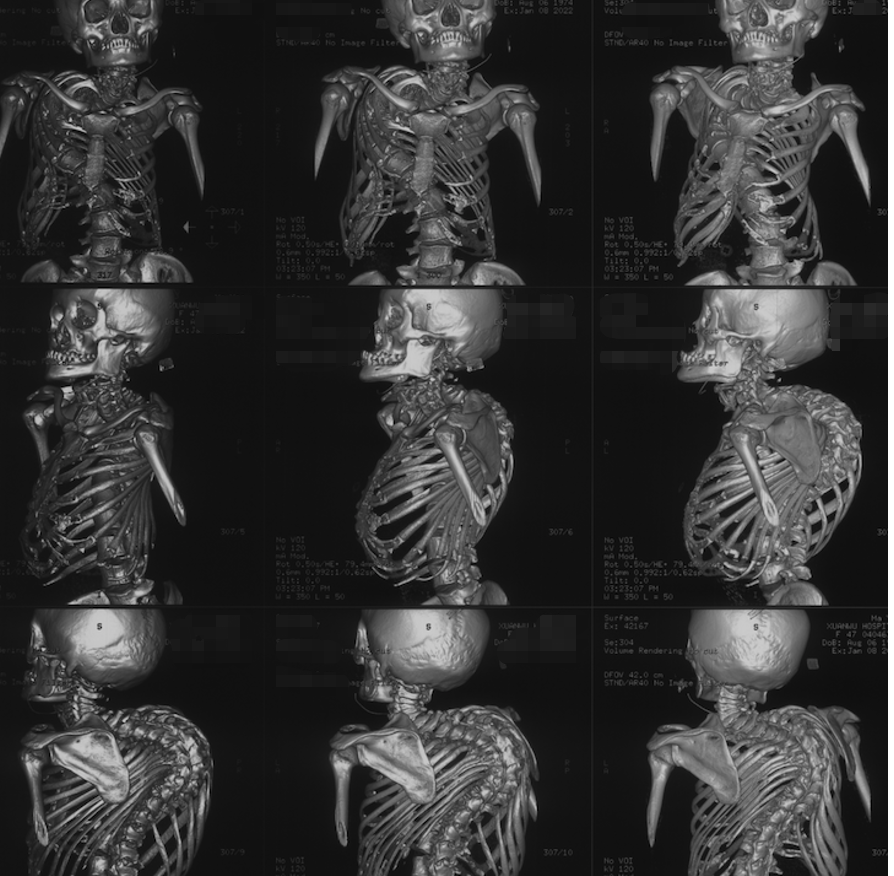

兰石骨科教学查房 脊髓空洞症

图片尺寸2000x2666